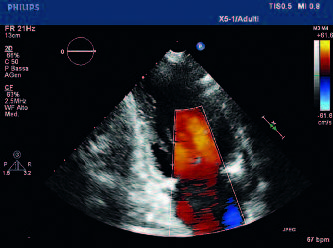

• Eseguire Ecocardiografia

Si sottolinea che in questa fase è ineludibile l’esecuzione di Ecocardiografia ed Emogasanalisi, esami che devono essere fruibili in tutti i Pronto Soccorso 24 ore su 24.